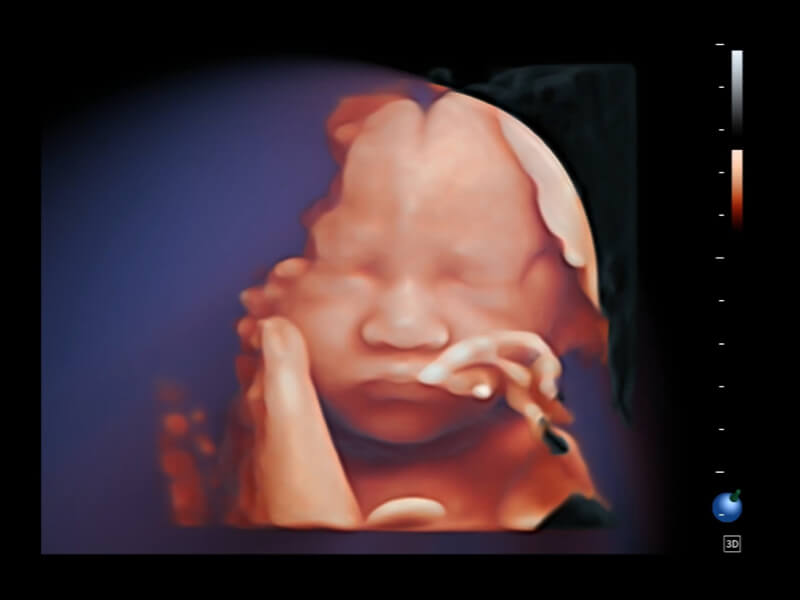

作為開(kāi)立醫(yī)療全新打造的超高端旗艦超聲產(chǎn)品,從探頭抬起喚醒開(kāi)啟掃查到多維探頭發(fā)射接收,通過(guò)先進(jìn)的場(chǎng)成像發(fā)射、自適應(yīng)聚合重建等技術(shù),基于RF Data原始射頻數(shù)據(jù)在圖像生成、高端功能等方面實(shí)現(xiàn)突破,為婦產(chǎn)科、兒科提供全方位臨床解決方案。

夢(mèng)溪?P80以“關(guān)愛(ài)女性”為基石,提供全方位的解決方案,量身定制以滿(mǎn)足女性的健康需求,涵蓋婦科、生殖健康檢查、產(chǎn)前篩查及產(chǎn)后康復(fù)等領(lǐng)域。